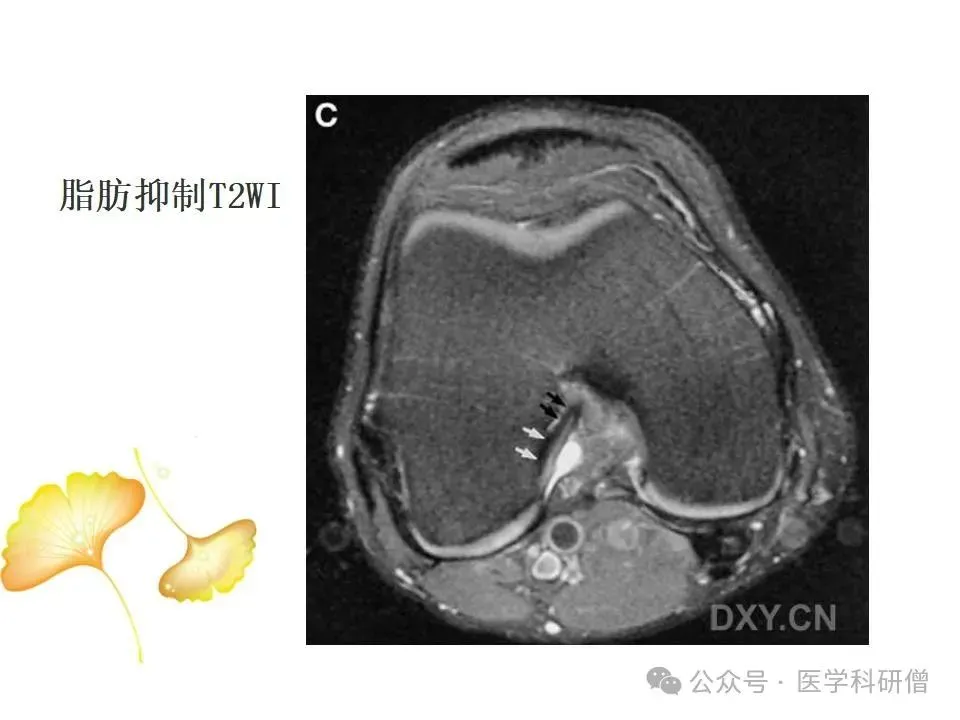

• T2加权像:对于显示水分和炎症特别敏感,能够显示韧带周围的水肿和炎症情况,对于诊断韧带损伤非常有帮助。

• 质子加权像和压脂像:这些技术能够提高图像对比度,更好地识别韧带和周围软组织的损伤情况。